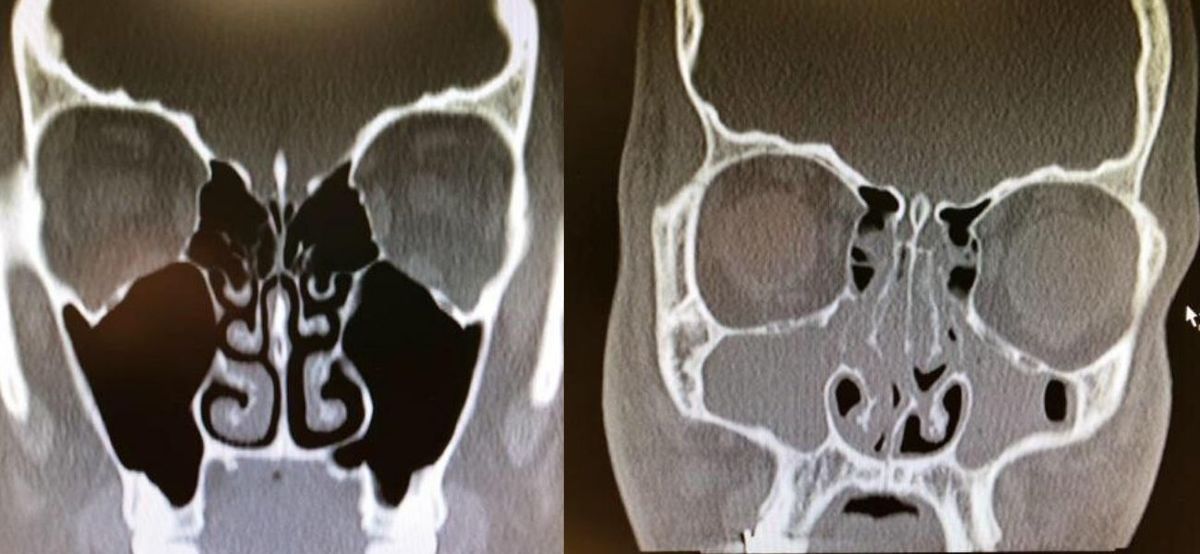

Xrays Of Congested And Un-congested Sinuses Will Make You Grateful For Air

congested and uncongested xray

This is really wild. This person had bad congestion and allergies so their sinuses were completely swelled up.

If this doesn't make you breathe a little easier then I don't know what will because I am feeling thankful for my un-congested sinuses right now.